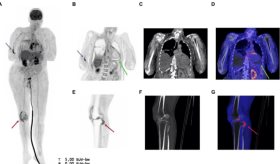

En cuanto al diagnóstico, si se sospecha un colangiocarcinoma, el médico puede realizar diversas pruebas como análisis de función hepática y del marcador tumoral CA 19-9, que pueden sugerir la presencia de cáncer.

También se emplean estudios por imágenes como ecografía, tomografía computarizada y resonancia magnética. En algunos casos se utiliza la colangiopancreatografía retrógrada endoscópica para observar directamente los conductos y tomar muestras o biopsias.

El objetivo principal fue reducir el volumen tumoral y mejorar la calidad de vida del paciente, permitiendo el drenaje adecuado de la vía biliar obstruida.

"Logramos impermeabilizar el ducto biliar de este paciente, ya le habíamos hecho intervenciones previas y el tumor estaba creciendo y estaba generando obstrucción del drenaje biliar, y con con los resultados obtenidos con la ablación, logramos abrir un espacio a ese drenaje normal que debe tener el ducto biliar y mejorar drenaje hepático." explicó.